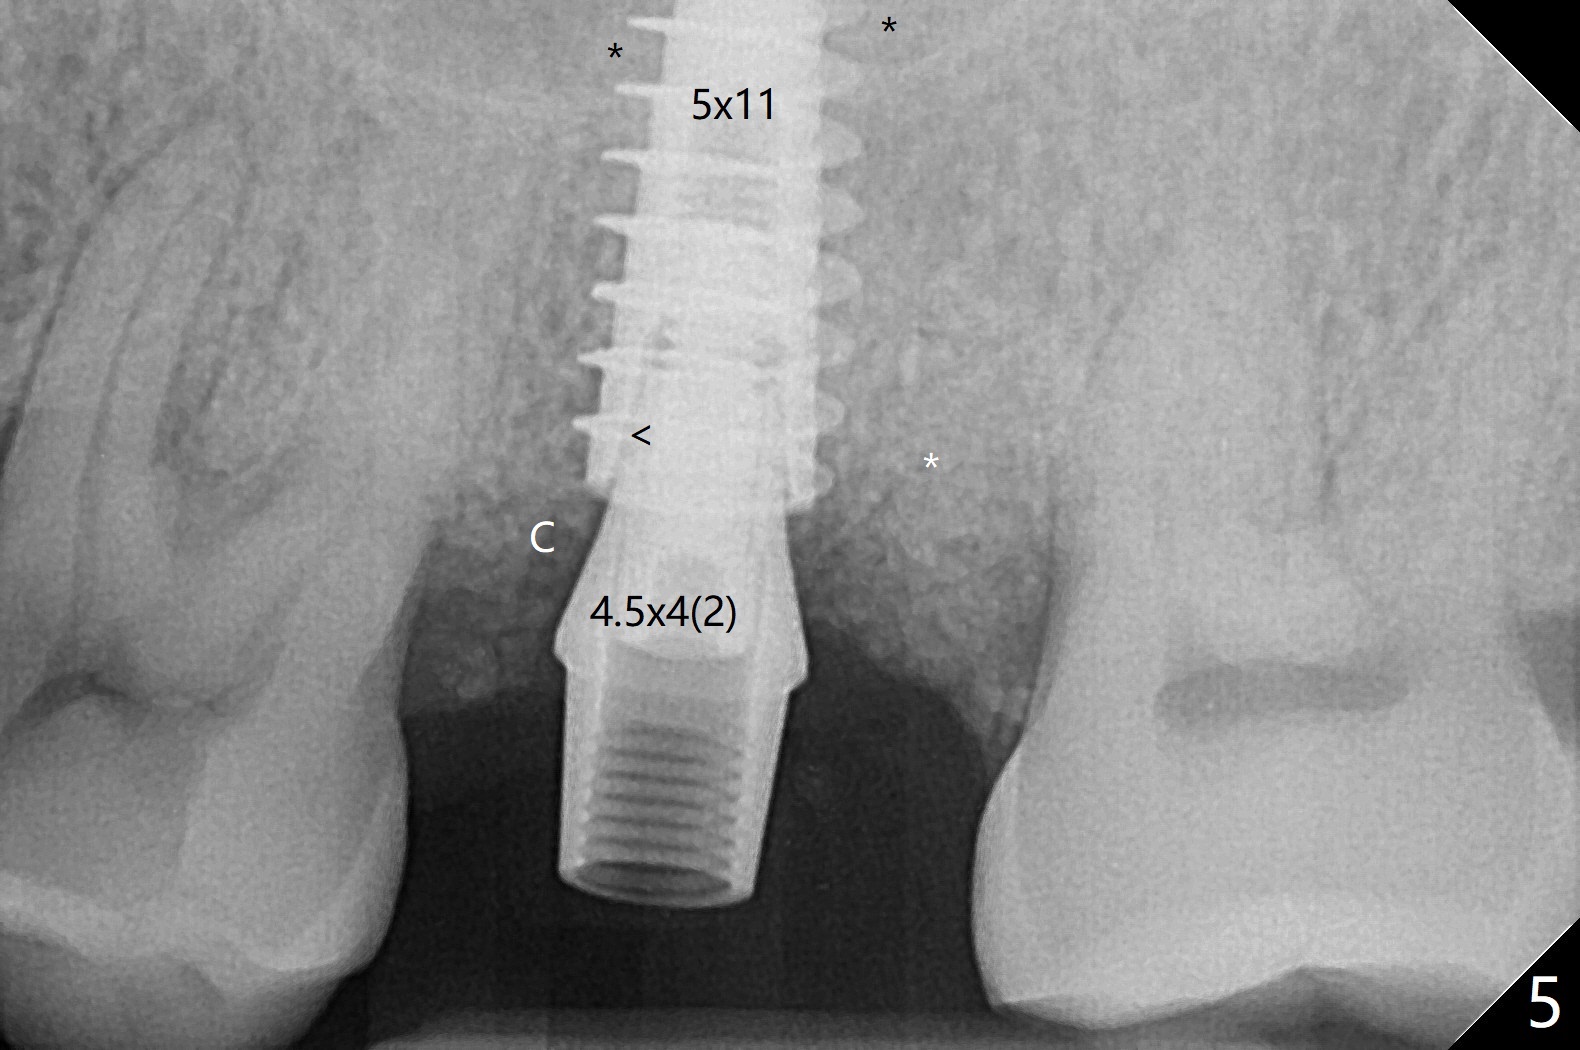

At #15, the sinus floor is initially perforated with modified drill sequence. With placement of PRF and bone graft in the osteotomy, the same 4.5x11 mm dummy implant is inserted to start sinus lift (Fig.4 *). When the dummy implant is removed, more bone graft is placed into the osteotomy and pushed into the sinus with the 5x11 mm final implant (Fig.5). Second round of bone graft is placed next to the implant before placing a 4.5x4(2) mm abutment, but the latter appears not to be seated completely, as indicated by the arrowhead. After use of 6 mm profile drill, a 4.5x4(3 (cuff)) mm abutment is able to be seated apparently completely without a gap (Fig.6 <). The third round of bone graft (Fig.6 *) is placed around the abutment to make sure that the underlying implant is fully covered to reduce periimplantitis in the future. The bone graft around the abutment disappears most coronally, while that around the implant remains 4 months postop (Fig.7). The implant is stable.